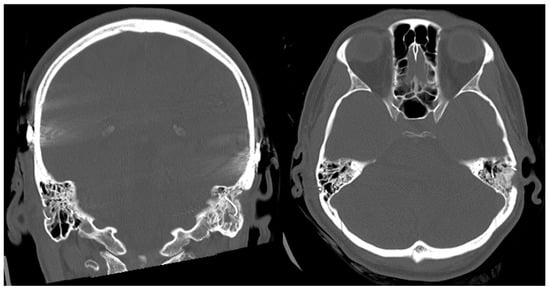

- Topsakal, V.; Heuninck, E.; Matulic, M.; Tekin, A.M.; Mertens, G.; Van Rompaey, V.; Galeazzi, P.; Zoka-Assadi, M.; van de Heyning, P. First Study in Men Evaluation of a Surgical Robotic Tool Providing Autonomous Inner Ear Access for Cochlear Implantation. Front. Neurol. 2022, 13, 804507. [Google Scholar] [CrossRef]

- Topsakal, V.; Matulic, M.; Assadi, M.Z.; Mertens, G.; Van Rompaey, V.; Van de Heyning, P. Comparison of the Surgical Techniques and Robotic Techniques for Cochlear Implantation in Terms of the Trajectories Toward the Inner Ear. J. Int. Adv. Otol. 2020, 16, 3–7. [Google Scholar] [CrossRef]

- Tekin, A.M.; Matulic, M.; Wuyts, W.; Assadi, M.Z.; Mertens, G.; van Rompaey, V.; Li, Y.; van de Heyning, P.; Topsakal, V. A New Pathogenic Variant in POU3F4 Causing Deafness Due to an Incomplete Partition of the Cochlea Paved the Way for Innovative Surgery. Genes 2021, 12, 613. [Google Scholar] [CrossRef]